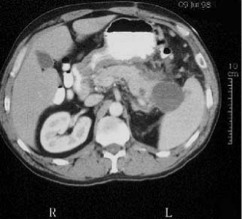

Acumulación aguda de liquido peripancreatico

-48h después del inicio de síntomas.

-solo un 15% evoluciona a seudoquiste con complicaciones.

Necrosis pancreática

-Realizar de 24 a 48h después de hospitalización

-Mediante aspiración percutanea determinar si es estéril o infectada

*NPE no es necesaria intervención qx.*

*NPI mortalidad de un 50%*